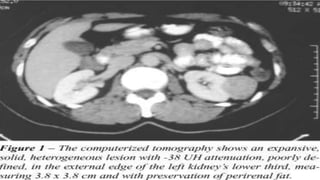

(a) Diffuse, huge,

ill-defined soft

tissue swelling. (b)

Contrast enhanced

computed

tomography scan

showing a well-

defined, lobulated,

hypodense seen

along the muscular

plane of left thigh.

Multiple enhancing

septae noted within

with no

calcifications. (c)

Anterior and lateral

view

(a) Diffuse, huge, ill-definedsoft tissue swelling. (b) Contrast enhanced computed tomography scan showing a well- defined, lobulated, hypodense seen along the muscular plane of left thigh. Multiple enhancing septae noted within with no calcifications. (c) Anterior and lateral view